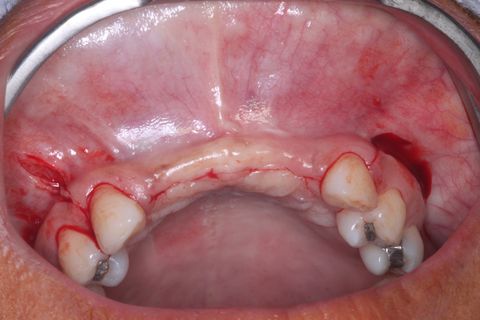

Foto Oclusal inferior

Foto Oclusal superior sem a Prótese Parcial removível

Foto oclusal aproximada, realçando o defeito ósseo na região vestibular

Paciente do sexo feminino, 32 anos e 10 mêses de idade, com ausência dos incisivos centrais e laterais superiores, associado a um defeito ósseo vestibular côncavo. Realizamos planejamento reverso, ou seja, enceramento diganóstico prévio para avaliação do defeito ósseo em termos de quantidade e do posicionamento final das próteses. A paciente foi submetido a um enxerto ósseo autógeno do ramo ascendente lado direito e fixação dos blocos ósseos na área receptora, com fixação dos mesmos através de parafusos de fixação com cabeça expandida Neodent. Após 6 meses foram instalados 4 implantes Neodent.